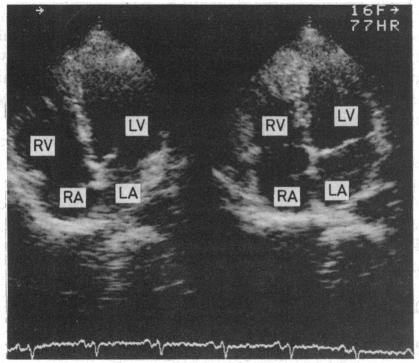

A 45 year old white man developed transient abnormal Q waves and ST segment elevation preceding left anterior fascicular block during exercise stress testing. The simultaneous disappearance of Q waves and fascicular block suggested that the abnormal Q waves were determined by an early septal conduction defect.

一名45岁白人男性在运动负荷试验中,于左前分支阻滞之前出现短暂异常Q波和ST段抬高。Q波与分支阻滞同时消失,提示异常Q波由早期间隔传导缺陷所致。